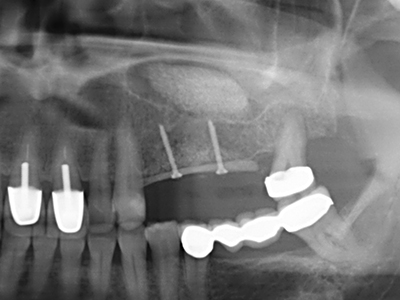

Indikation: Sinuslift

Die Präparation des lateralen Fensters bei der externen Sinusbodenelevation stellt gerade für chirurgisch unerfahrene Implantologen eine große Herausforderung dar. Die knöcherne Bedeckung der Kieferhöhle ohne eine Verletzung der darunterliegenden Schneider’schen Membran abzutragen ist dabei nur ein Teil der Operation – nach Schaffung eines ausreichenden Zugangs muss die Kieferhöhlenschleimhaut vorsichtig mobilisiert werden, um Raum für das einzubringende Material bzw. die Implantate zu schaffen. In dieser Indikation ist die Piezochirurgie zweierlei hilfreich: zum einen kann durch Verwendung diamantierter Instrumente eine selektive Knochenabtragung erfolgen und die darunter liegende Schleimhaut bleibt bei vorsichtiger Vorgehensweise intakt. Zum anderen unterstützen die Ultraschallfrequenzen zusätzlich eine komplikationslose Ablösung der Schleimhaut – sie werden durch spezielle stumpfe Ansätze in den Spaltraum zwischen Schleimhaut und Kieferhöhlenboden übertragen (Cassetta, Ricci et al. 2012, Pereira, Gealh et al. 2014) (Rickert, Vissink et al. 2013). So erscheint es nicht verwunderlich, dass in aktuellen Übersichtsarbeiten über die externe Sinusbodenelevation neben der Verwendung von rauen Implantatoberflächen und dem Einsatz von Knochenersatzmaterialien auch der Einsatz von piezoelektronischen Geräten als positiv bewertet wird (Wallace, Tarnow et al. 2012).